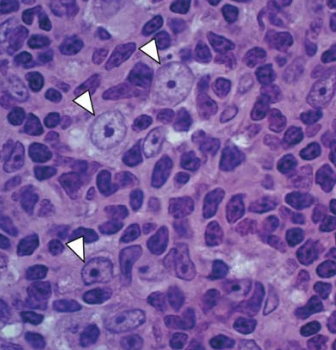

High Endothelial Venules

arrows

lympohocytes

arrow HEADS

high endothelial cells

High endothelial (post-capillary) venule

red arrow